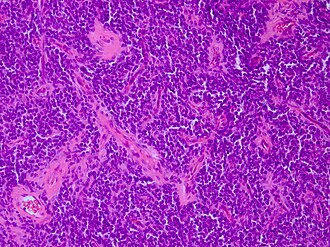

CNS primitive neuroectodermal tumour H&E stain. | |

Microscopic

Features:

- Small round blue cell tumour.

- Focal differentation into astrocytic, neuronal or ependymal phenotypes possible.

- May have true rosettes (slit-like/oval).

- Growth in streams or palisades possible ("spongioneuroblastoma").

- Vascular endothelial proliferations.

- Fibrillary background in tumours with advanced neuronal maturation (ganglioneuroblastomas).

- Variable mitotic activity.